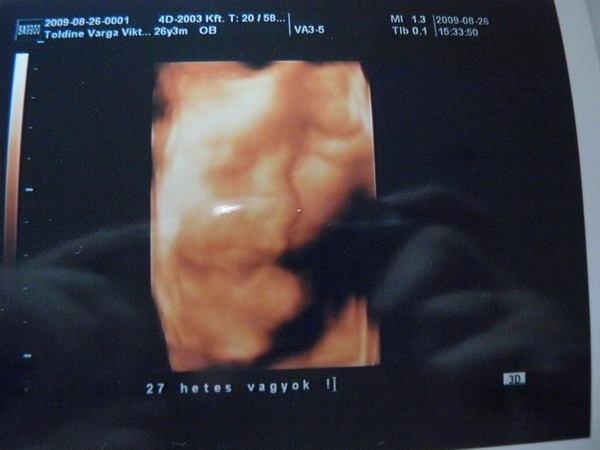

Ma voltunk dokinál, megnézett, megfelelünk a 30. hétnek, jelenleg farfekvésűek vagyunk. Azt mondta a doki ha megfordulna még természetes szülés is lehet. A cukor miatt plusz dolgokat is nézett, de azt mondta a korának megfelelő a fiam, nem nagyobb. Most 1400 g körüli a súlya. Mikor anyukámnak mondtam, ő keveselte, de szerintem nincs gond, fejlődik ő, s mire eljön az idő majd megfelelő súlyú lesz